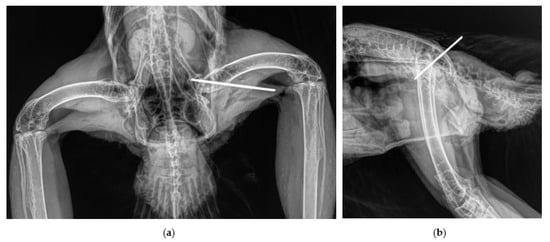

2.2. Surgical Procedure and Post-Surgery Management